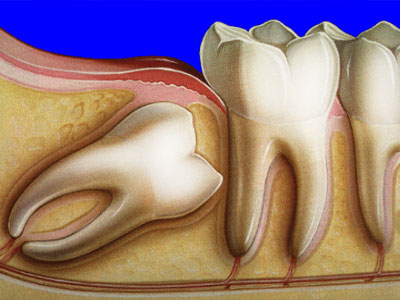

Причина возникновения болей, также кроется в особенностях прорезывания зубов мудрости. Очень часто стоматологи сталкиваются с клинической картиной, когда зуб мудрости растет горизонтально, при таком типе роста и формирования, коронковая часть восьмого зуба может толкать, задевать, и разрушать, корни соседних седьмых зубов, что неизменно приводит к приступам боли.

Горизонтальный рост зуба мудрости